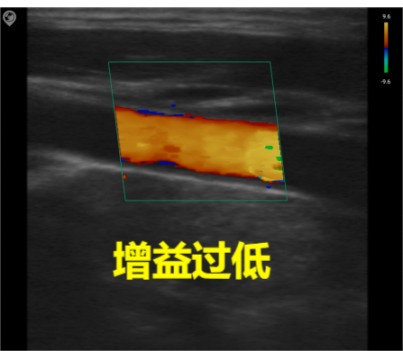

Common parameter adjustment for C mode

Gain

Total gain: Adjusts the sensitivity of blood flow signals, with the gain value displayed in real-time on the image parameter area of the screen.

Image quality: Excessive gain obscures the image with chaotic color spots, while insufficient gain may lead to loss of blood flow signals. During actual adjustment, the optimal setting is to clearly distinguish red and blue blood flow without color aliasing.